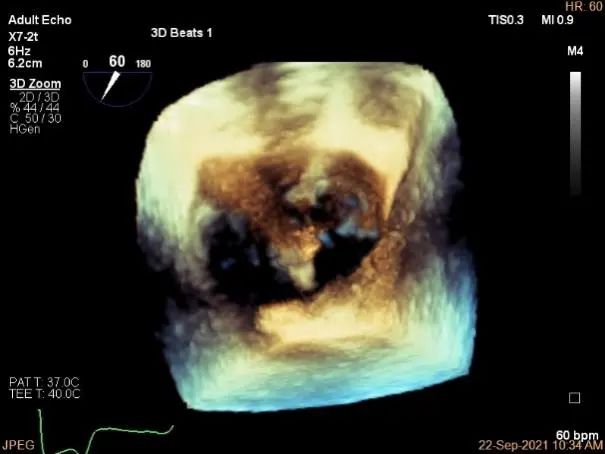

三维评估两个夹子位置

3D-color再次确定未见残余分流

3D:P1区脱垂并腱索断裂,Width:11.4mm

3D-color:重度MR,4级

3d确认夹子位置在P1区

3d-color确认残余分流情况